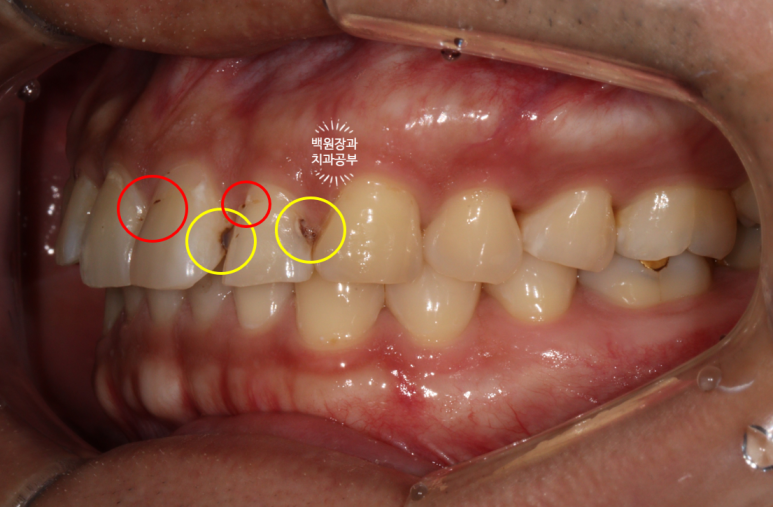

노란색 원으로 표시해둔 곳은 앞니 옆면 (인접면) 충치이고, 빨간색 원으로 표시해둔 곳은 기존 레진충전의 변색입니다.

변색은 표면을 다듬기! 충치는 레진으로 떼우기!

치과용 파노라마 엑스레이를 보시면, 아마도.. 기존의 교정 유지장치 때문에 옆면 cleansing이 어렵게 되어 충치가 생겼음을 예상해볼 수 있습니다.